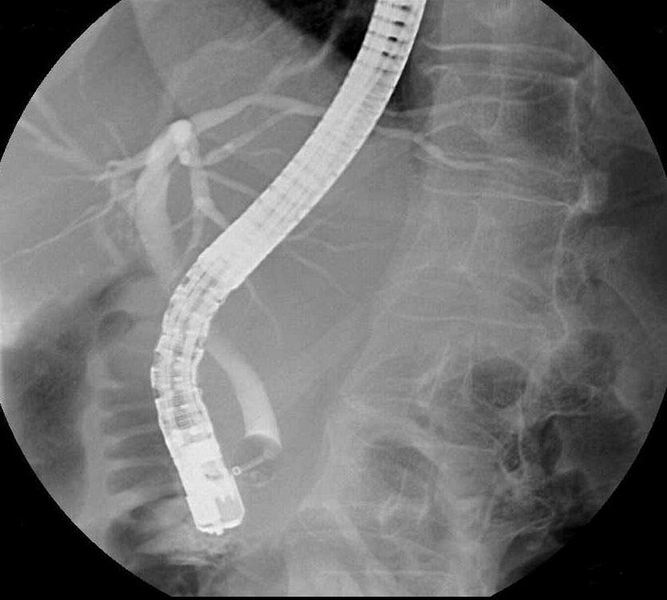

Thorax – Abdomen – Schedel – CWZ – DWZ – LWZ – Bekken – Full Spine – Schouder – Bovenarm – Elleboog – Onderarm – Pols – Hand – Heup – Bovenbeen – Knie – Onderbeen – Enkel – Voet – Full Leg – Transit – Colonografie – E.R.C.P. – I.V.P. – Cystografie – Hysterografie

Colonografie